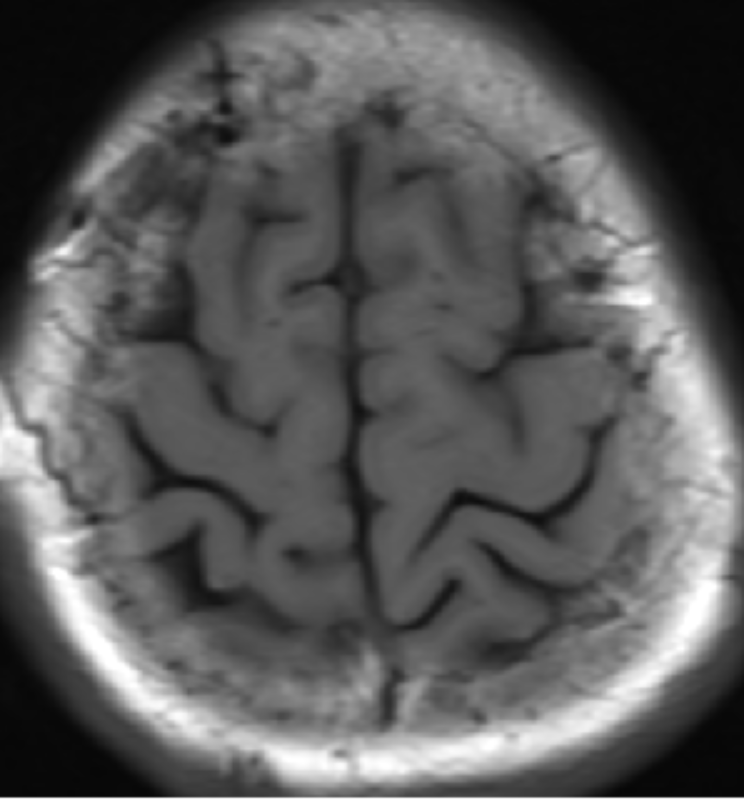

2015-4-1 MRI

2015-4-1

2015-4-3